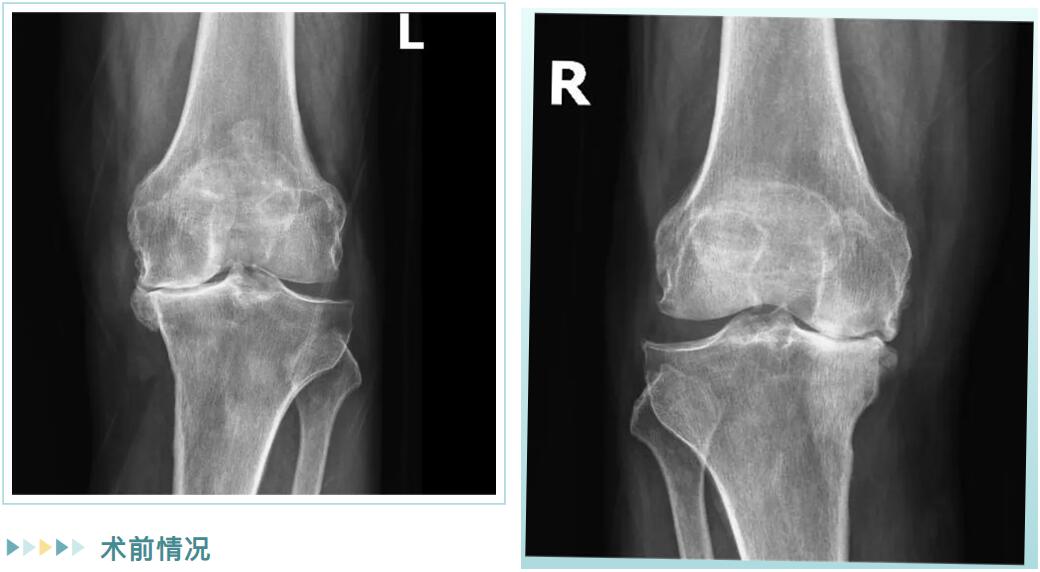

經(jīng)詳細(xì)檢查,邵阿伯被診斷為“雙膝重度骨性關(guān)節(jié)炎”。在保守治療無(wú)效后,羅院長(zhǎng)團(tuán)隊(duì)為他量身定制了治療方案:雙側(cè)膝關(guān)節(jié)內(nèi)側(cè)單髁置換術(shù)。

術(shù)前情況